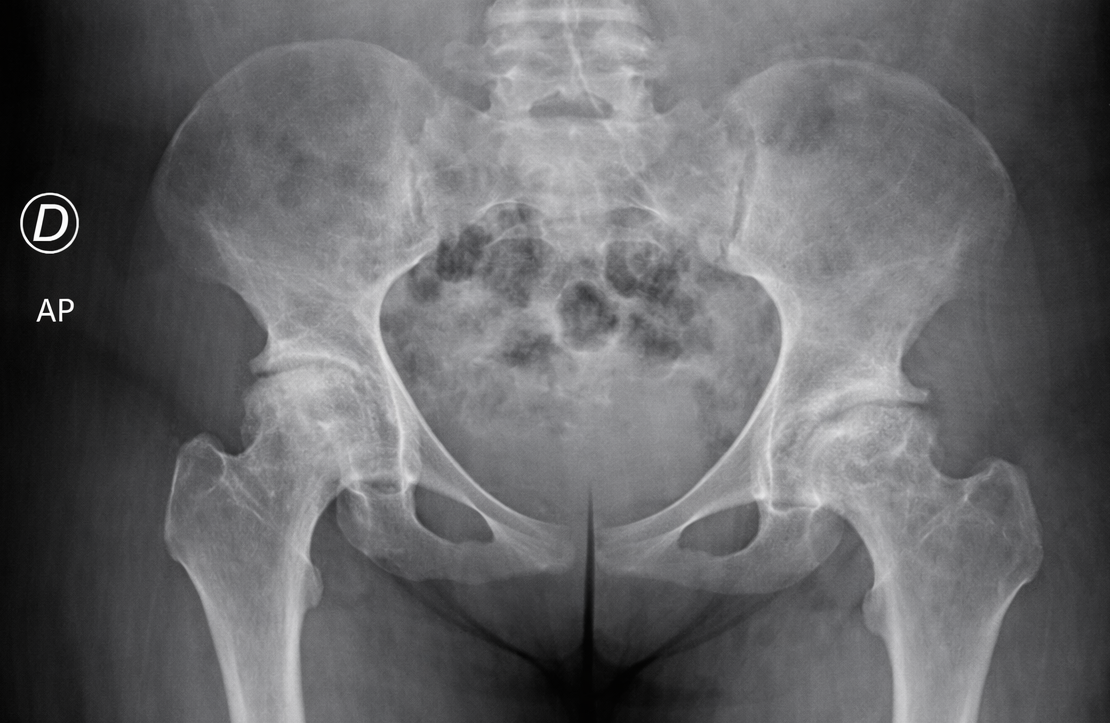

• Challenges of total hip arthroplasty in patients with sickle cell disease

Elido Perez, MD; Delfilio Martinez, MD; Jose Taveras, MD

Sickle cell anemia (SCA), the most common and severe form of the disease, arises from a point mutation in the β-globin gene, leading to the production of abnormal hemoglobin S (HbS).